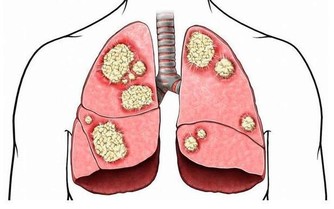

原來「心肌梗塞」不是血管太窄堵阻塞不通!真相竟是?! 醫生現身說法,一定要分享出去!!

原來心肌梗塞不是心臟血管太狹窄堵塞血不流通,請認真看完影片、真的

新光醫院洪惠風醫師解析什麼是"心肌梗塞", 大家抽空看一下喔 ! 值得瞭解。